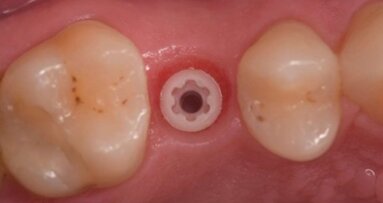

Pcube: in cosa consiste e quali vantaggi offre? Diciamo anzitutto che Pcube sta per “Planned Prosthetic Placement”, a sottolineare che questo sistema a dime componibili può essere usato per riabilitazioni full-arch in chirurgia guidata allo scopo di ottenere il posizionamento della protesi in perfetta occlusione con l’arcata antagonista, studiato a priori in fase di progettazione. Per fare ciò è necessario andare oltre la solita, semplice dima chirurgica ad appoggio dentale o mucoso, creando un sistema di guide interconnesse che permetta di replicare in modo esatto sul paziente reale tutto quanto pianificato nel paziente digitale, grazie alla combinazione dei dati provenienti dai moderni dispositivi diagnostici. In tal senso, il primo e fondamentale elemento è la dima “base”, utilizzabile anche per le procedure di resezione ossea che, anche quando quella fase è conclusa, non viene rimossa e che, dunque, diventa il riferimento spaziale fisso cui ancorare le guide successive. Dopo le eventuali operazioni di apertura del lembo e avulsione degli elementi terminali, su di essa viene avvitata una dima specifica per il posizionamento implantare e, successivamente ancora, una dima che funziona da carrier per il provvisorio. Una delle grandi sfide dal punto di vista tecnologico è stata rappresentata dal fatto di dover garantire al clinico una buona visibilità in ogni configurazione, soprattutto per facilitare la rimozione degli elementi terminali e la gestione dei tessuti molli. Per raggiungere tale scopo abbiamo ideato una combinazione di materiali fresati e da stampa 3D, per minimizzare gli ingombri delle dime senza comprometterne la resistenza: ciò agevola l’apertura dei lembi e l’irrigazione e, inoltre, offre un piano per la guida dell’osteotomia.

Questa combinazione di tecnologie - stampa 3D e fresatura – rappresenta il vero game changer nei confronti di altre soluzioni di tipo componibile. Pcube rappresenta allora una delle massime espressioni delle tendenze che più hanno caratterizzato l’evoluzione tecnica in implanto-protesi degli ultimi anni: la ricerca costante di una protesizzazione veloce o addirittura a carico immediato, la riduzione dei tempi di trattamento e il fatto di porre il paziente, sempre più cosciente delle proprie necessità e con aspettative sempre più alte, al centro del progetto terapeutico a 360°. Come in tutte le evoluzioni, nulla sarebbe stato possibile senza l’innovazione offerta dalla tecnologia: in tal senso, ad esempio, gli sviluppi di quella legata al mondo digitale ci hanno permesso di poter costruire un paziente virtuale sempre più accurato, ottimizzando la raccolta dei dati ed elaborandoli al fine di ottenere un manufatto protesico sempre migliore grazie, altro esempio, all’evoluzione della stampa 3D. A chiudere il cerchio interviene poi tutto ciò che succede in ODS: l’internalizzazione di competenze per la modellazione, la dotazione di macchine con altissimo livello di qualità di stampa, di quelle per il fresaggio, l’anodizzazione del titanio e la produzione di manufatti provvisori per addizione e sottrazione e, infine, la connessione da e per il centro produttivo attraverso un avanzato software di comunicazione. Aggiungo infine che, nel rispetto di una logica di offerta “integrata”, la soluzione Pcube offre il massimo in termini di precisione e risparmio di tempo nel momento in cui viene impiegata con un impianto sviluppato specificamente per il carico immediato: Fixo.

Cosa intende? In una riabilitazione full arch a carico immediato il clinico impiega sempre molto tempo nella fase di posizionamento e controllo dei cosiddetti Multi-Unit-Abutment: si tratta sicuramente di uno dei momenti più critici e “faticosi” di questa tipologia di intervento. Per dare seguito alle tantissime richieste di miglioramento di questa fase, Oxy Implant ha sviluppato Fixo, un impianto one-piece progettato specificamente per le riabilitazioni a carico immediato con approccio computer guidato. Senza dilungarmi troppo, posso dire che il MUA integrato nel corpo unico di Fixo ha un chamfer di diametro inferiore ai 5 mm, quindi adatto al posizionamento attraverso le sleeve delle guide chirurgiche; che il design e la finitura del suo collo ne rendono meno traumatico l’inserimento e facilitano la guarigione dei tessuti molli; che la sua vite protesica di tipo M 1.8 offre la possibilità di serraggio a 30 N/cm. Questo prodotto ci ha permesso di dialogare con tanti nuovi professionisti, cui l’utilizzo di Fixo ha notevolmente semplificato i protocolli quotidiani, determinando il risparmio di tempo operatorio per il clinico e maggior flessibilità protesica per il tecnico. Si tratta insomma di un prodotto innovativo, esempio perfetto del Made in Italy applicato all’implantologia dentale.